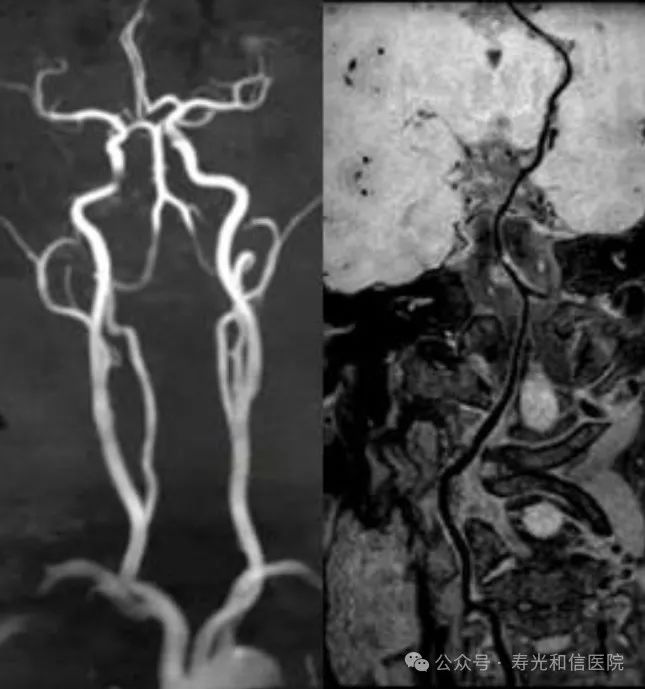

头颈部一体化血管成像

亮血:血管狭窄筛查。黑血:血管壁斑块成像。